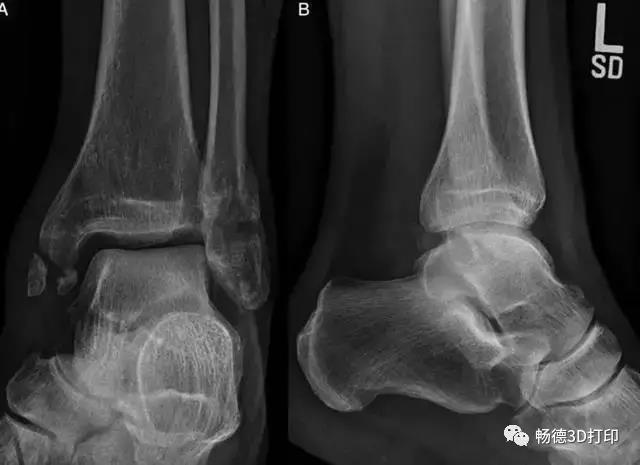

上图为:50 岁女性,车祸后出现左外踝疼痛,保守治疗不缓解

上图为:左图示该患者左足情况,提示腓骨距骨骨质移位,右图是患者右足正常关节间隙情况 。